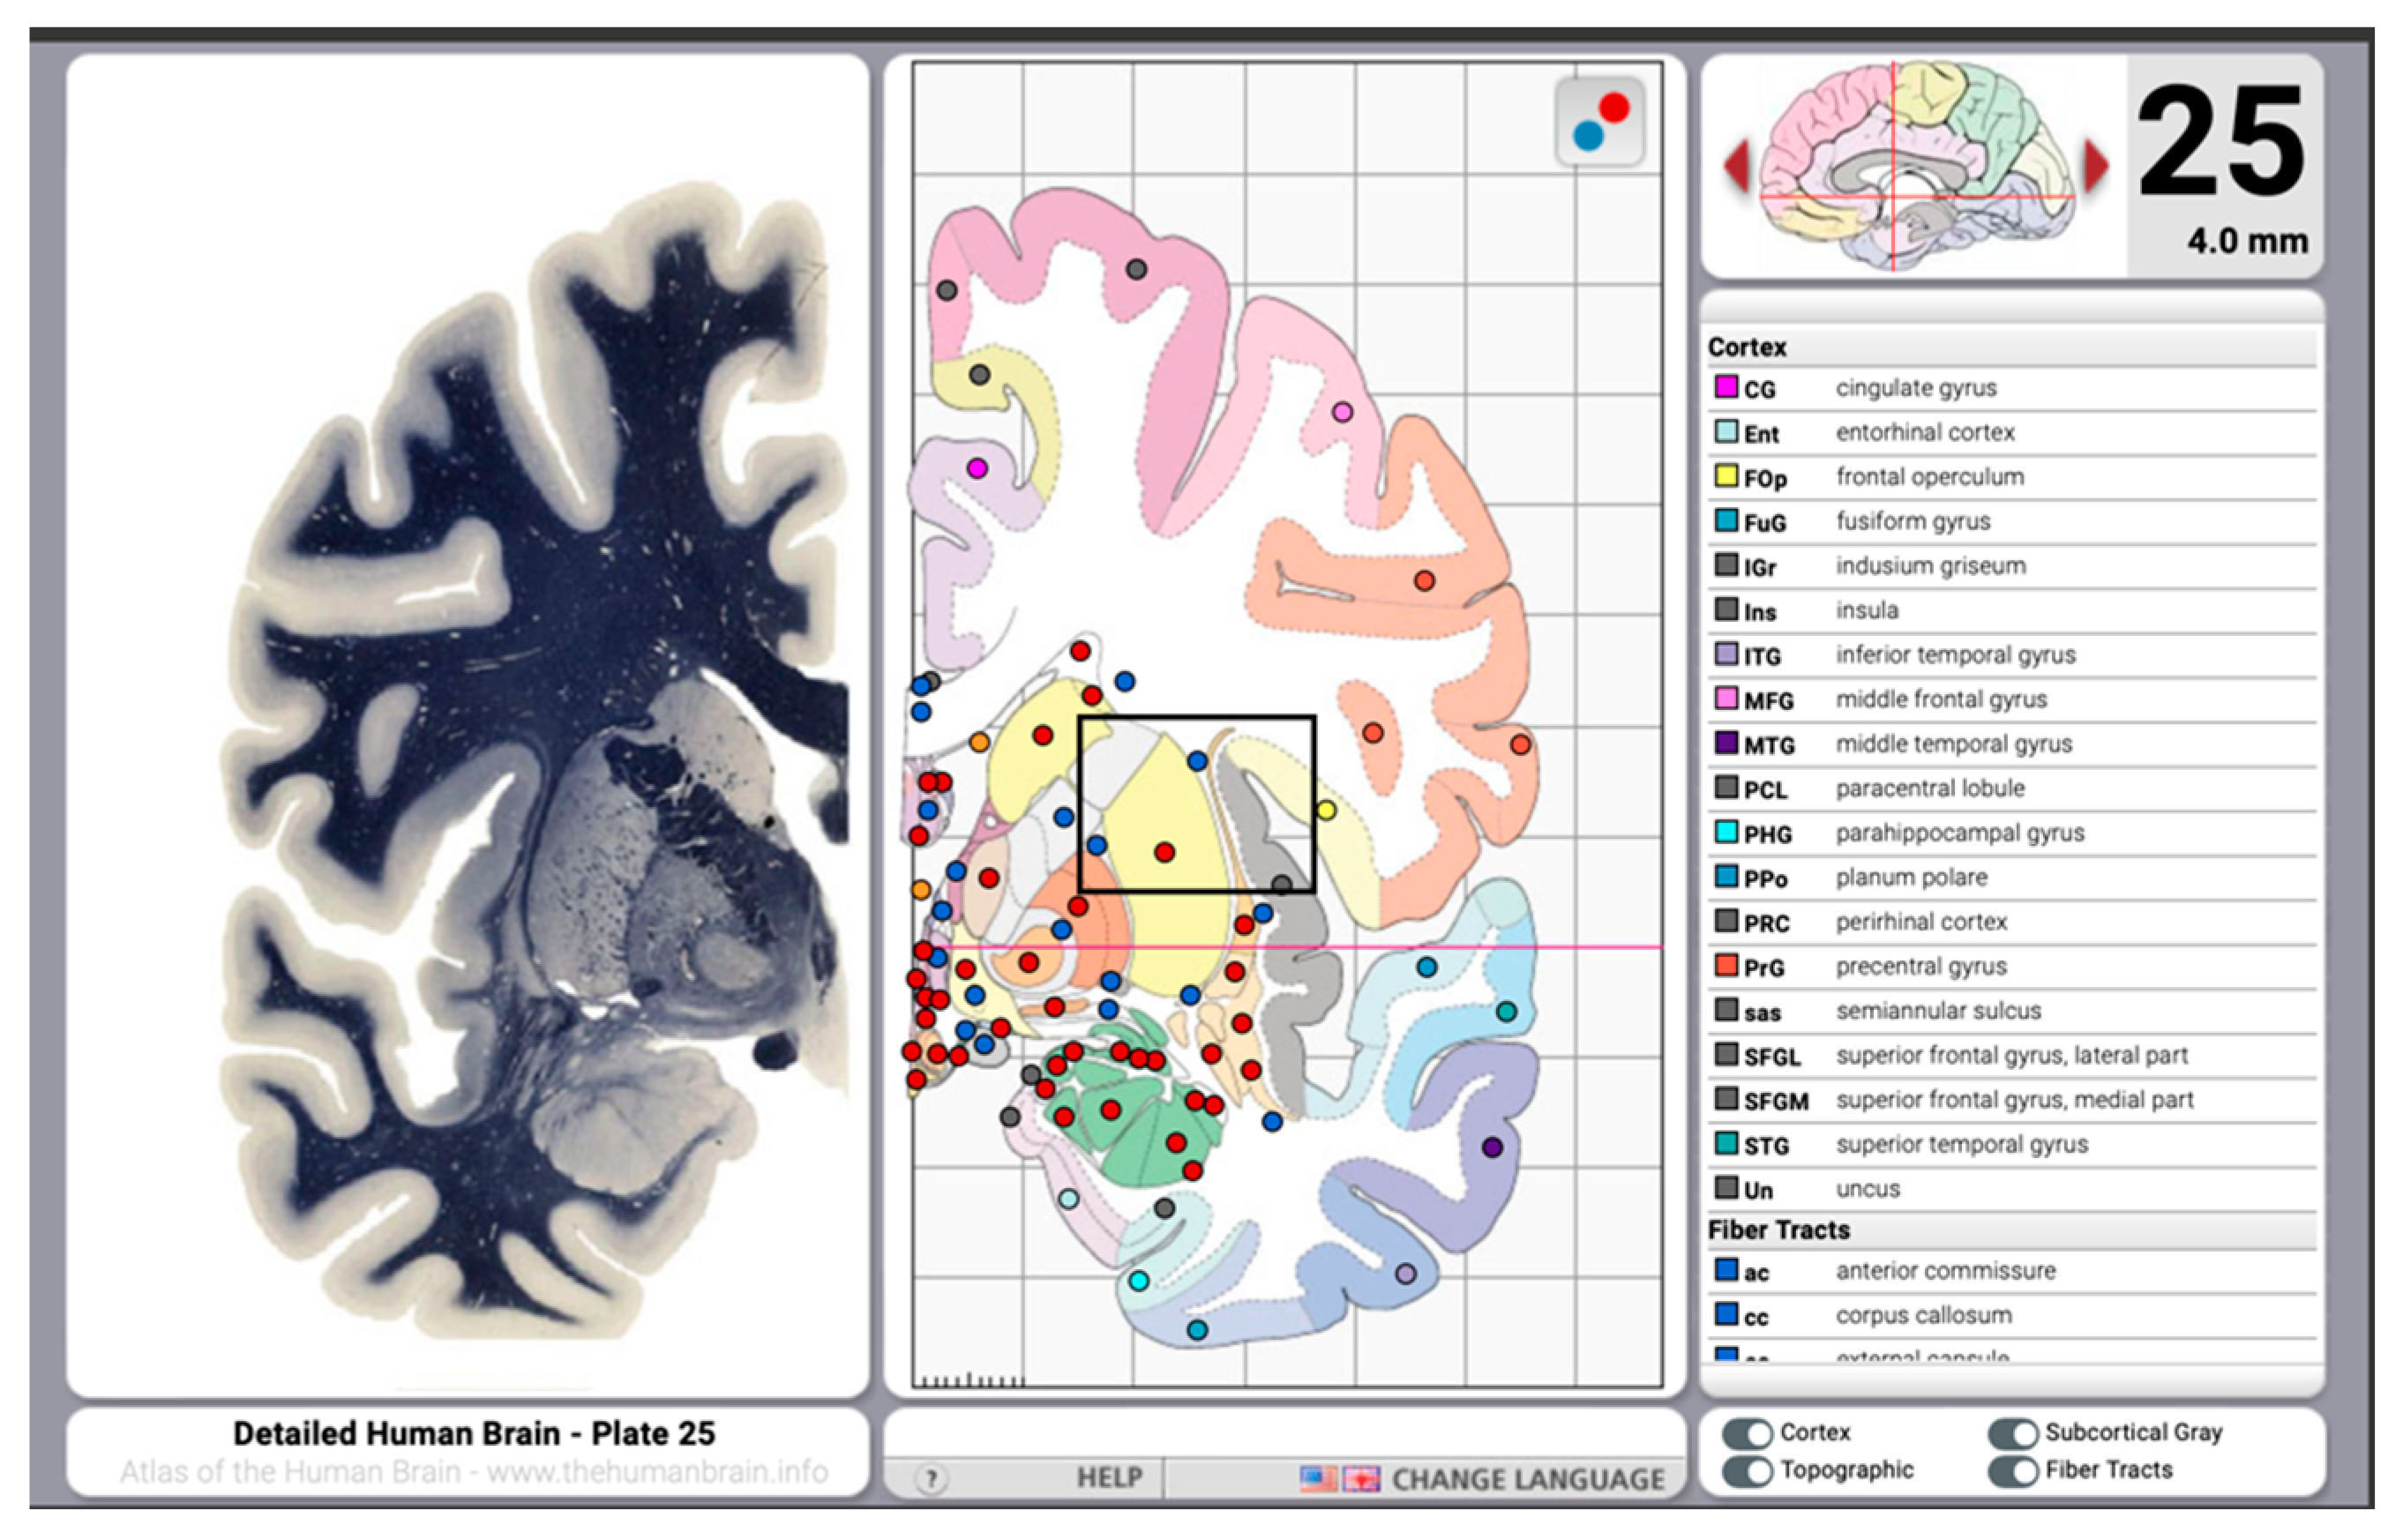

8. Digital Histological Atlases